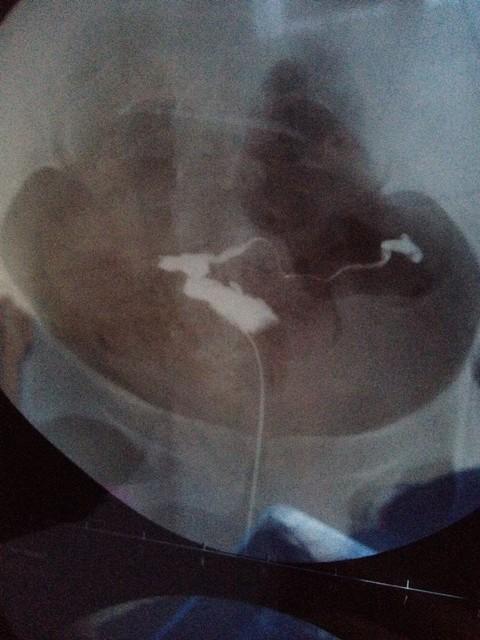

全市独家排粪造影检查帮您揪出便秘的“罪魁祸首”